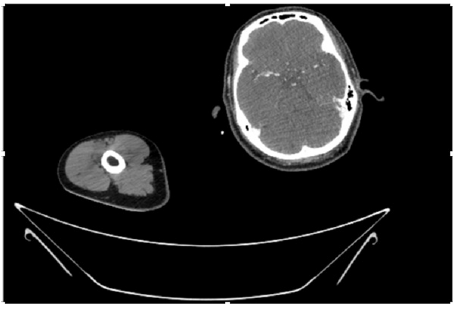

55-years-old chronic smoker had acute, severe pain in the right upper limb for one week; it was cold upto mid arm with skin discoloration. He also noticed numbness and weakness of movement of elbow joint. He underwent below elbow amputation in February 2023 for acute ischemia of left upper limb. He was a current chronic smoker; 15 pack year. General condition was weak; temperature was normal; blood pressure was 100/60mmHg; heart rate was 92/minutes with sinus rhythm; SpO2 was 97% on air; heart was normal. In lower extremities, all peripheral pulses were intact. Local Examination of right upper limb revealed as follows: tenderness; coldness; discoloration; decreased motor function and sensory modalities. Axillary, brachial and radial pulses were not palpable. Hand-held Doppler failed to detect any signal in arterial system; therefore, we arranged for emergency embolectomy. complete occlusion of right upper limb arterial system Full blood count showed high hemoglobin (14.6gm%); normal total WBC and platelet count. Coagulation profile was normal. Parenteral unfractionated heparin, antibiotics, tramadol, proton-pump inhibitors, anti-platelets and HMG CoA reductase inhibitors were given. Doppler ultrasound demonstrated complete occlusion of right upper limb arterial system. CT Angiogram illustrated occlusion of subclavian artery downwards on both sides. Figures 1-14 shows complete occlusion of right subclavian artery without collaterals. On Day ‘2’ of admission, the patient passed black tarry stool for 3 times. However, the vital signs were stable; blood pressure was 100/60mmHg; heart rate was 92/min; SpO2 was 97% on air; the abdomen was soft and not tender. Above elbow amputation was done on Day ‘2’ of admission. Intra-operative findings were as follows: (1) no active bleeding at brachial artery; (2) thrombosis along brachial artery; (3) muscle color and consistency were not healthy.

Figure 4: CT Angiogram at neck showing normal brachio-cephalic trunk, common carotid artery, and narrow right subclavian artery.

Figure 5: CT Angiogram at neck showing normal brachio-cephalic trunk, common carotid artery, and narrow right subclavian artery.

Figure 6: CT Angiogram at neck showing brachio-cephalic trunk, common carotid artery and narrow right subclavian artery.

Figure 7: CT Angiogram at neck showing brachio-cephalic trunk, common carotid artery and narrow right subclavian artery.

Figure 10: CT Angiogram at upper arm showing totally occluded right axillary artery; normal internal carotid artery and external carotid artery.